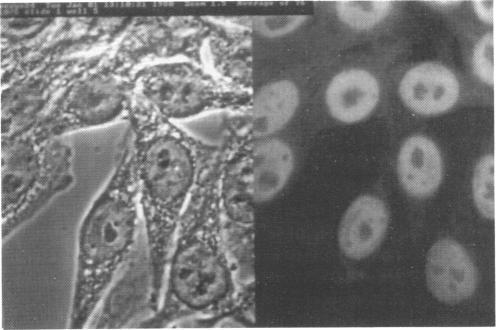

Binding of pentraxins to different nuclear structures: C-reactive protein binds to small nuclear ribonucleoprotein particles, serum amyloid P component binds to chromatin and nucleoli.

Binding of the human pentraxin plasma proteins, C-reactive protein (CRP) and serum amyloid P component (SAP), to the nuclei of human cells was studied using whole acute phase serum as the source of the proteins and confocal immunofluorescence microscopy. CRP and SAP clearly bound to distinct, different structures. Double staining with MoAbs to the Sm D and Sm B/B' components of small nuclear ribonucleoproteins confirmed that CRP bound exclusively to these particles. As expected, SAP bound to chromatin and, in addition, binding to the nucleolus was observed for the first time. These interactions demonstrated under relatively physiological conditions, with native pentraxins unseparated from serum and with nuclear constituents in situ, are likely to be of functional importance in vivo.